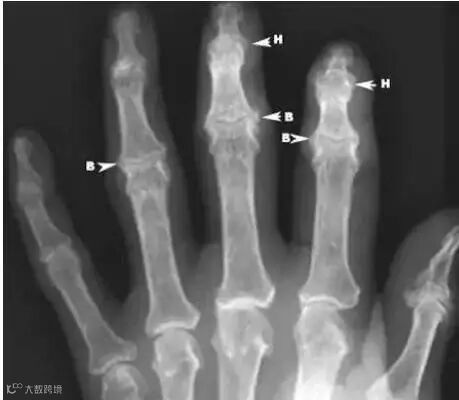

指间(趾间)关节出现骨质增生,往往是因为指间关节骨性关节炎,指间关节的软骨变性和骨质肥大增生,形成近节指间关节的布夏尔氏结节(Bouchard's nodes)和远节指间关节的希伯登氏结节(Heberden's nodes)。